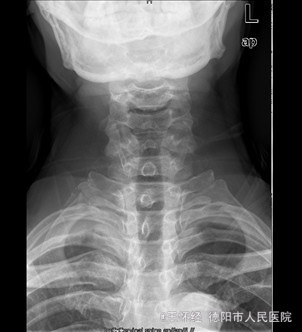

患者男,52岁,因“车祸伤后右肩部、右胸壁疼痛伴右上肢活动障碍1+天”入院。入院1+天前,患者因车祸伤致右肩部疼痛、有胸壁疼痛、右上肢活动障碍、无法上抬,无明显麻木,右胸锁关节处可见一明显隆起硬块、压痛明显,同时自觉少许呼吸困难,我院急诊行X光片示“右胸锁关节脱位”,遂收住我科。

查体:右侧胸锁关节处叩压痛明显,可扪及一隆起、质硬,右侧胸壁乳头周围肿胀,右肩外展因胸锁关节处疼痛而受限受限。 辅查:X片及CT提示示右侧胸锁关节向前脱位、双侧第一肋骨骨折

初步诊断:车祸伤:1.右侧胸锁关节前脱位;2.双侧第一肋骨骨折。 诊疗计划:右侧胸锁关节脱位切开复位,锚定固定修复关节囊及周围韧带。